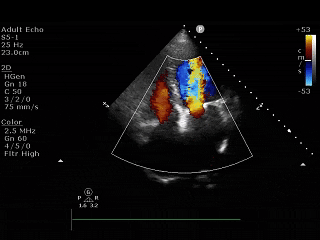

起搏器植入后:四腔心视图、左心室短轴视图和测量参数

1个月随访时,超声心动图评估显示肺动脉压力正常(详见表1)。利尿剂停用,临床改善明显:双下肢水肿完全消退,6分钟步行距离从156米增加至205米,NYHA Class得分提高至75分。同时,患者的NYHA心功能分级从III级改善为II级。